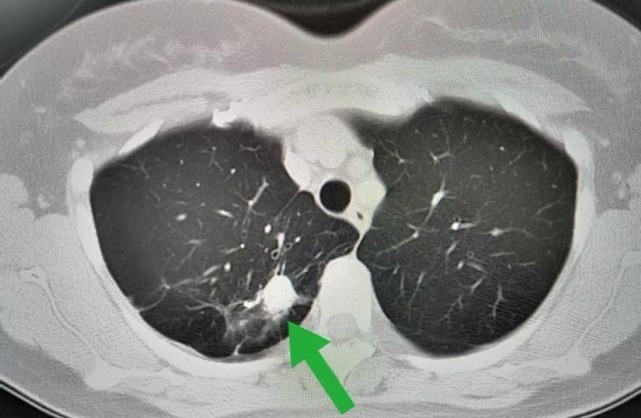

根据病变部位和病情程度不同,肺结节大致分为两种,一种是良性肺结节,另一种则是恶性肺结节。